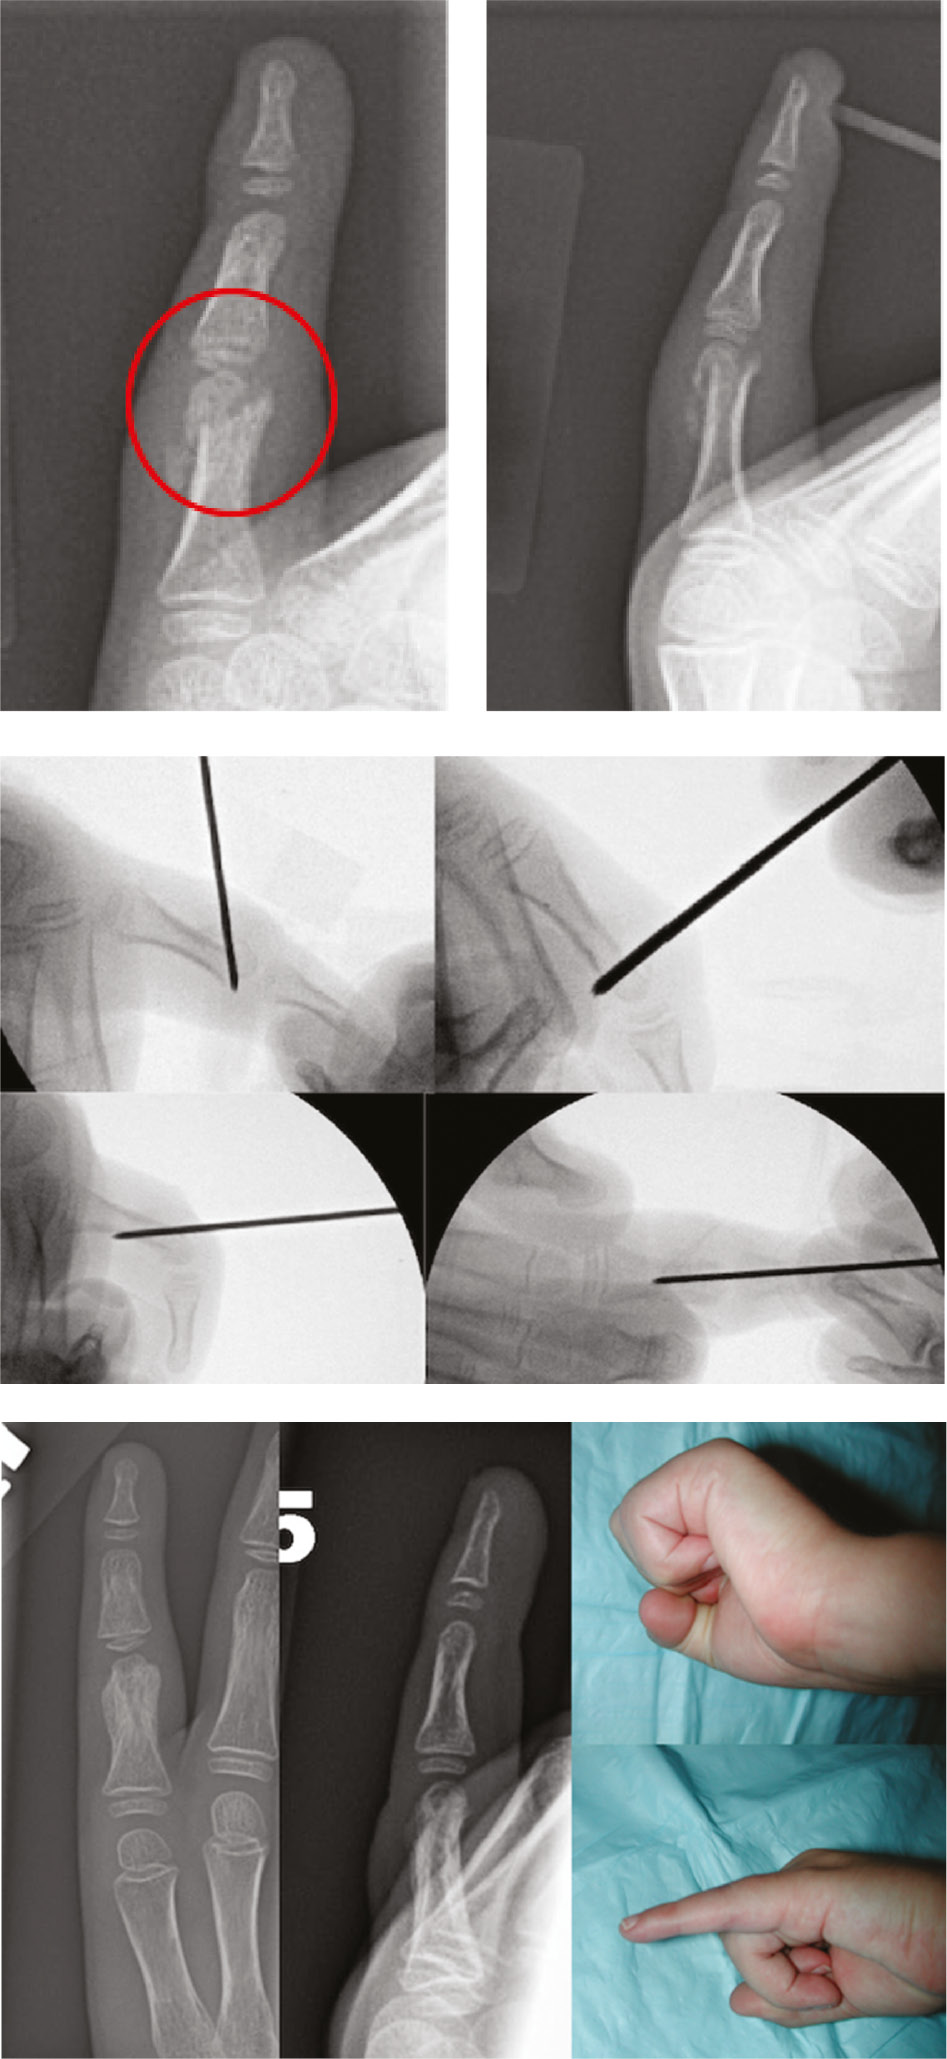

The incidence of pediatric phalangeal fractures spikes in early adolescence and corresponds with initiation of participation in contact sports.54 Salter-Harris type II fractures of the proximal phalanx are the most common type of phalangeal injury in children due to the intrinsic weakness of the physis compared to its surrounding structures.54 Surgical treatment is indicated for displaced intraarticular or unstable fractures (Figure 13).

Figure 13. A 7-year-old with an intraarticular fracture that required closed reduction and percutaneous reduction and pinning.

In the operating room, closed reduction is attempted. If successful, stability is then assessed by ranging the finger. If the fracture is determined to be unstable, percutaneous fixation can be achieved through two 0.9 mm K-wires, one ulnar and one radial, that are run in an antegrade and crossed fashion. Patients are subsequently casted.55 Wires can also be used to osteotomize or reduce phalangeal neck fractures (Figure 14).

Figure 14. This 5-year-old sustained a phalangeal neck fracture 10 days prior to clinic appointment. The fracture was partially healed and closed reduction in the OR was not possible. He underwent percutaneous leveraging of the fracture and stabilization with dorsal buttress pin.